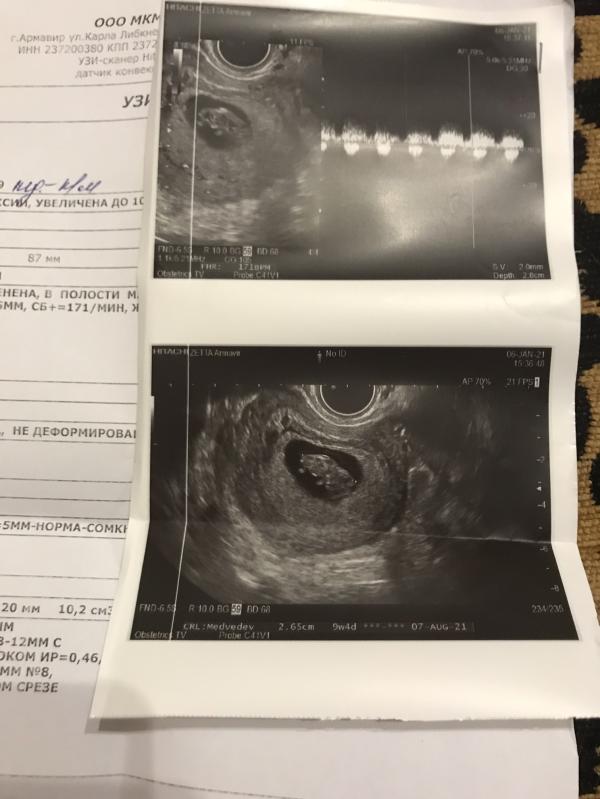

Сегодня была на узи 9 недель перед постановкой на учёт. Что скажите ?